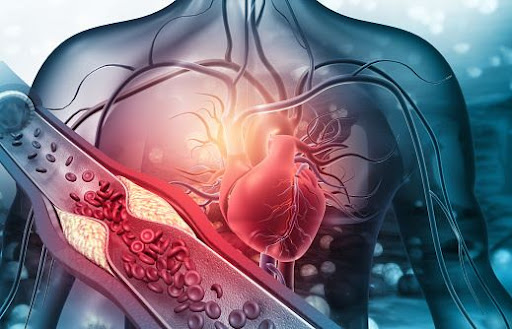

심장은 인간의 몸에서 특정한 위치에 자리잡고 있으며, 그 구조와 기능에 따라 여러 중요한 역할을 수행합니다. 심장은 흉강 중앙에 위치해 있으며, 두 개의 폐 사이에 자리잡고 있는 '가슴뼈'(sternum)와 가까운 위치에 있습니다. 즉, 심장은 왼쪽으로 살짝 치우친 형태로, 아래쪽은 횡격막(diaphragm)이라는 근육에 의해 지지받고 있습니다. 이러한 구조는 심장이 외부 압력으로부터 보호받을 수 있도록 도와줍니다.

심장은 네 개의 주요 구역으로 나뉘며, 각각의 구역은 특정한 혈액 순환 기능을 맡고 있습니다. 이 네 개의 구역은 우심방(right atrium), 우심실(right ventricle), 좌심방(left atrium), 좌심실(left ventricle)로 구성됩니다. 이들 각 구역은 서로 다른 기능을 하며, 신체의 혈액 흐름을 조절합니다.

심장은 단순히 혈액을 펌프하는 역할 외에도 여러 기타 중요한 기능을 수행하고 있습니다. 그 중 하나는 영양소와 산소를 공급하고, 노폐물을 제거하여 신체의 항상성(homeostasis)을 유지하는 것입니다. 심장이 정상적으로 작동하지 않으면, 다양한 질병이 발생할 수 있습니다.

심장은 지속적으로 심박수에 따라 수축과 이완을 반복합니다. 이 과정을 통해 혈액이 심장에서 신체의 각 부분으로 전달되며, 다시 심장으로 돌아오는 순환을 만들어냅니다. 심장은 이 과정을 통해 산소와 영양소를 공급하고, 이산화탄소와 기타 노폐물을 제거하는 역할을 합니다.